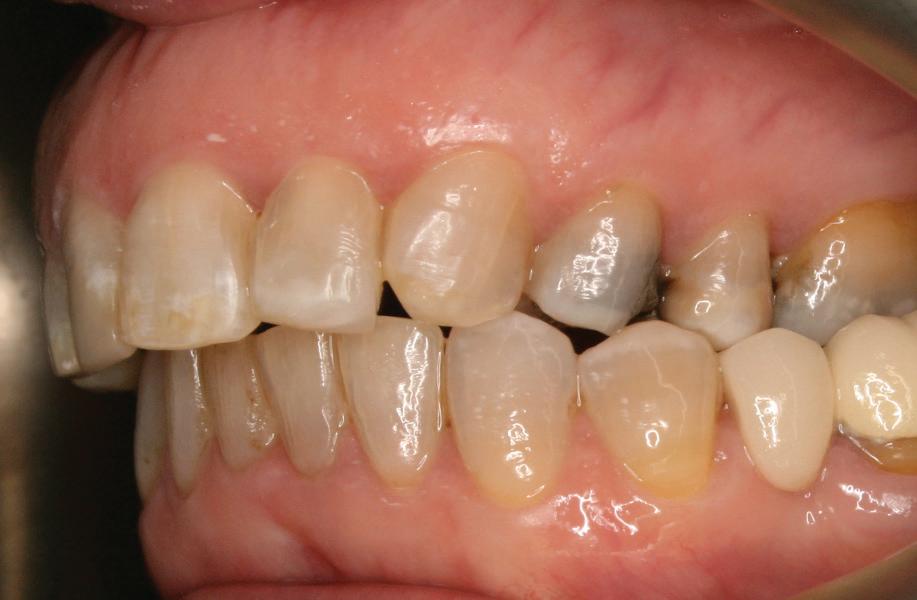

Effective communication following overseas treatment

Una Man, dento-legal adviser at the Dental Defence Union (DDU), explains how to

and communicate with patients who have had treatment outside the UK

It is becoming more common for dental professionals to encounter patients who require follow-up care after receiving treatment outside of the UK. This could be for a variety of reasons, for example:

• Those who have needed to seek urgent treatment only and/or further planned treatment whilst living, working or holidaying abroad

• Those who have moved to the UK from another country where they have undergone previous treatment

• Those who have travelled outside the UK as a ‘dental tourist’, to undergo specific dental treatment